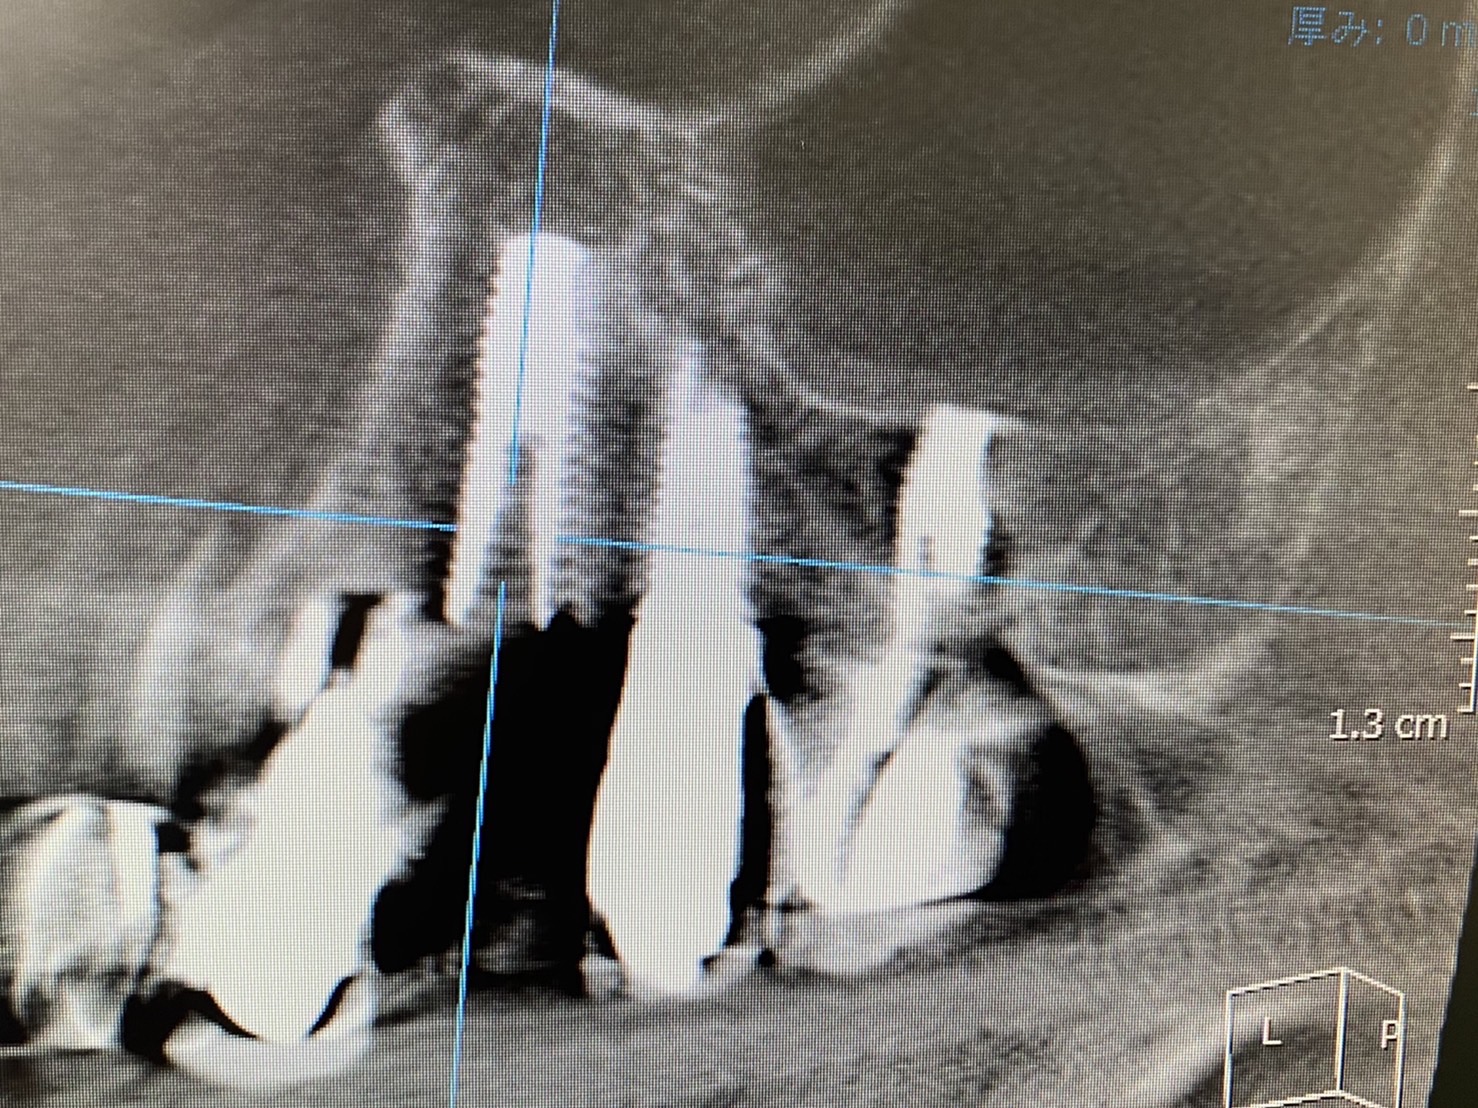

本日は、朝からインプラントオペ

右上4番

抜歯から埋入まで15分で終わり

即時荷重目安値ボーダーギリギリでしたので、ウィング付きで対処 力の分散、連結による

加強固定ですね!

6wにISQ計測し下降なければ印象です!

120Nまでありますが、理想は60から80Nぐらいの力で埋入し、深度調整してます

骨には弾性がありますから、ダメージなく大変良好です!